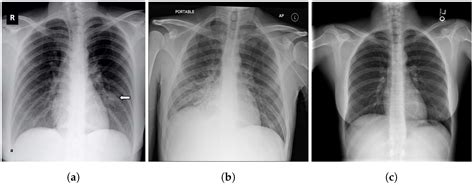

Diagnosis of Walking Pneumonia

Diagnosing walking pneumonia involves a combination of physical examination, medical history, and diagnostic tests. Doctors may order the following tests:

• Chest X-ray: To visualize the lungs and detect any inflammation or fluid buildup.

Diagnosis of Bronchitis

Diagnosing bronchitis involves a physical examination and medical history. Doctors may also order the following tests:

• Chest X-ray: To rule out pneumonia or other lung conditions.